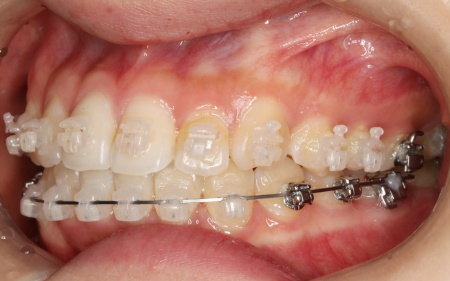

・ワイヤー矯正

歯の表面にブラケットと呼ばれるボタン状の装置を接着し、そこにワイヤーを通して歯を移動させる方法です。

患者様は目立たない治療方法を望まれていたため、ブラケットには白く目立ちにくい「セラミックブラケット」を選択しました。

まずは歯の表面にセラミックブラケットを装着し、ワイヤー矯正で歯を全体的に移動させます。

歯並びがある程度正しい位置に並んだら、マウスピース矯正で微調整を行いました。

歯の移動が完了したあとは定期的に経過を確認しながら、後戻りを防ぐためのリテーナー(保定装置)を継続して使用いただき、治療を終了しました。